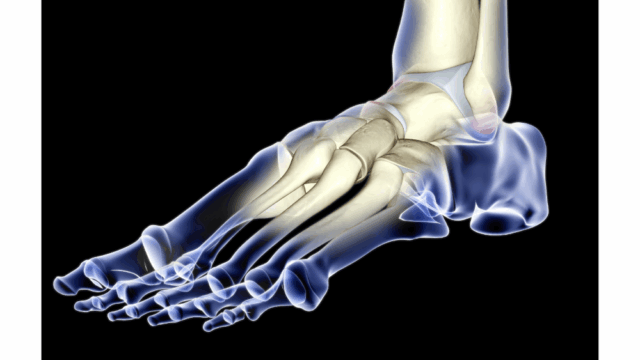

อุ้งเท้าแบน